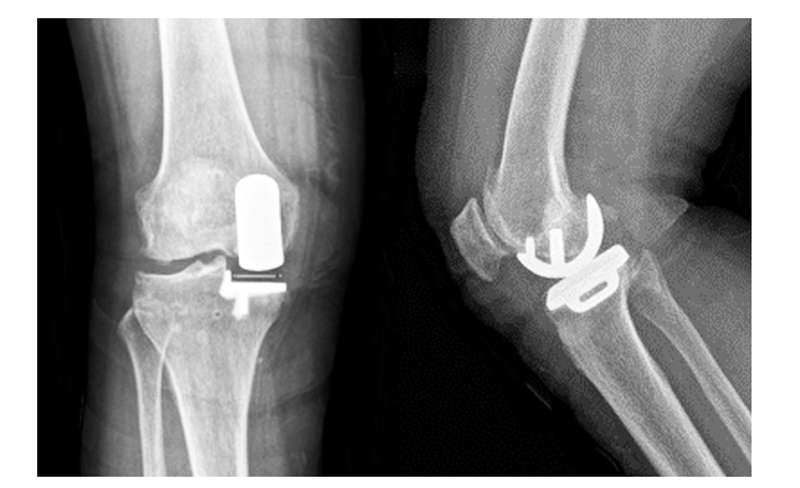

(2)65岁女性患者,以右膝关节疼痛3年、加重半年为主诉入院,入院查体右下肢内翻畸形8°,膝关节内侧间隙压痛阳性,外侧无压痛,浮髌试验阴性,髌骨研磨试验 阴 性,抽 屉 试 验 阴 性,ROM10°~130°,诊断为右膝关节前内侧骨关节炎,行 Oxford活 动 平 台 内 侧 单髁置换术。术后24h内间断 冰 敷,给予预 防 感 染、消 肿 止 痛及抗凝 治 疗,术 后24h康复师指导助行器辅助下床活动,术后1个月膝关 节 HSS评 分 由62分升至81分,KSS评 分 由50分升至85分,内侧疼痛消失,手术效果良好。手术前后影像学资料见图3~4。

图3术前 X线片示内侧间隙呈骨对骨改变

图4术后 X线片示假体位置良好,大小合适,活动垫片在位